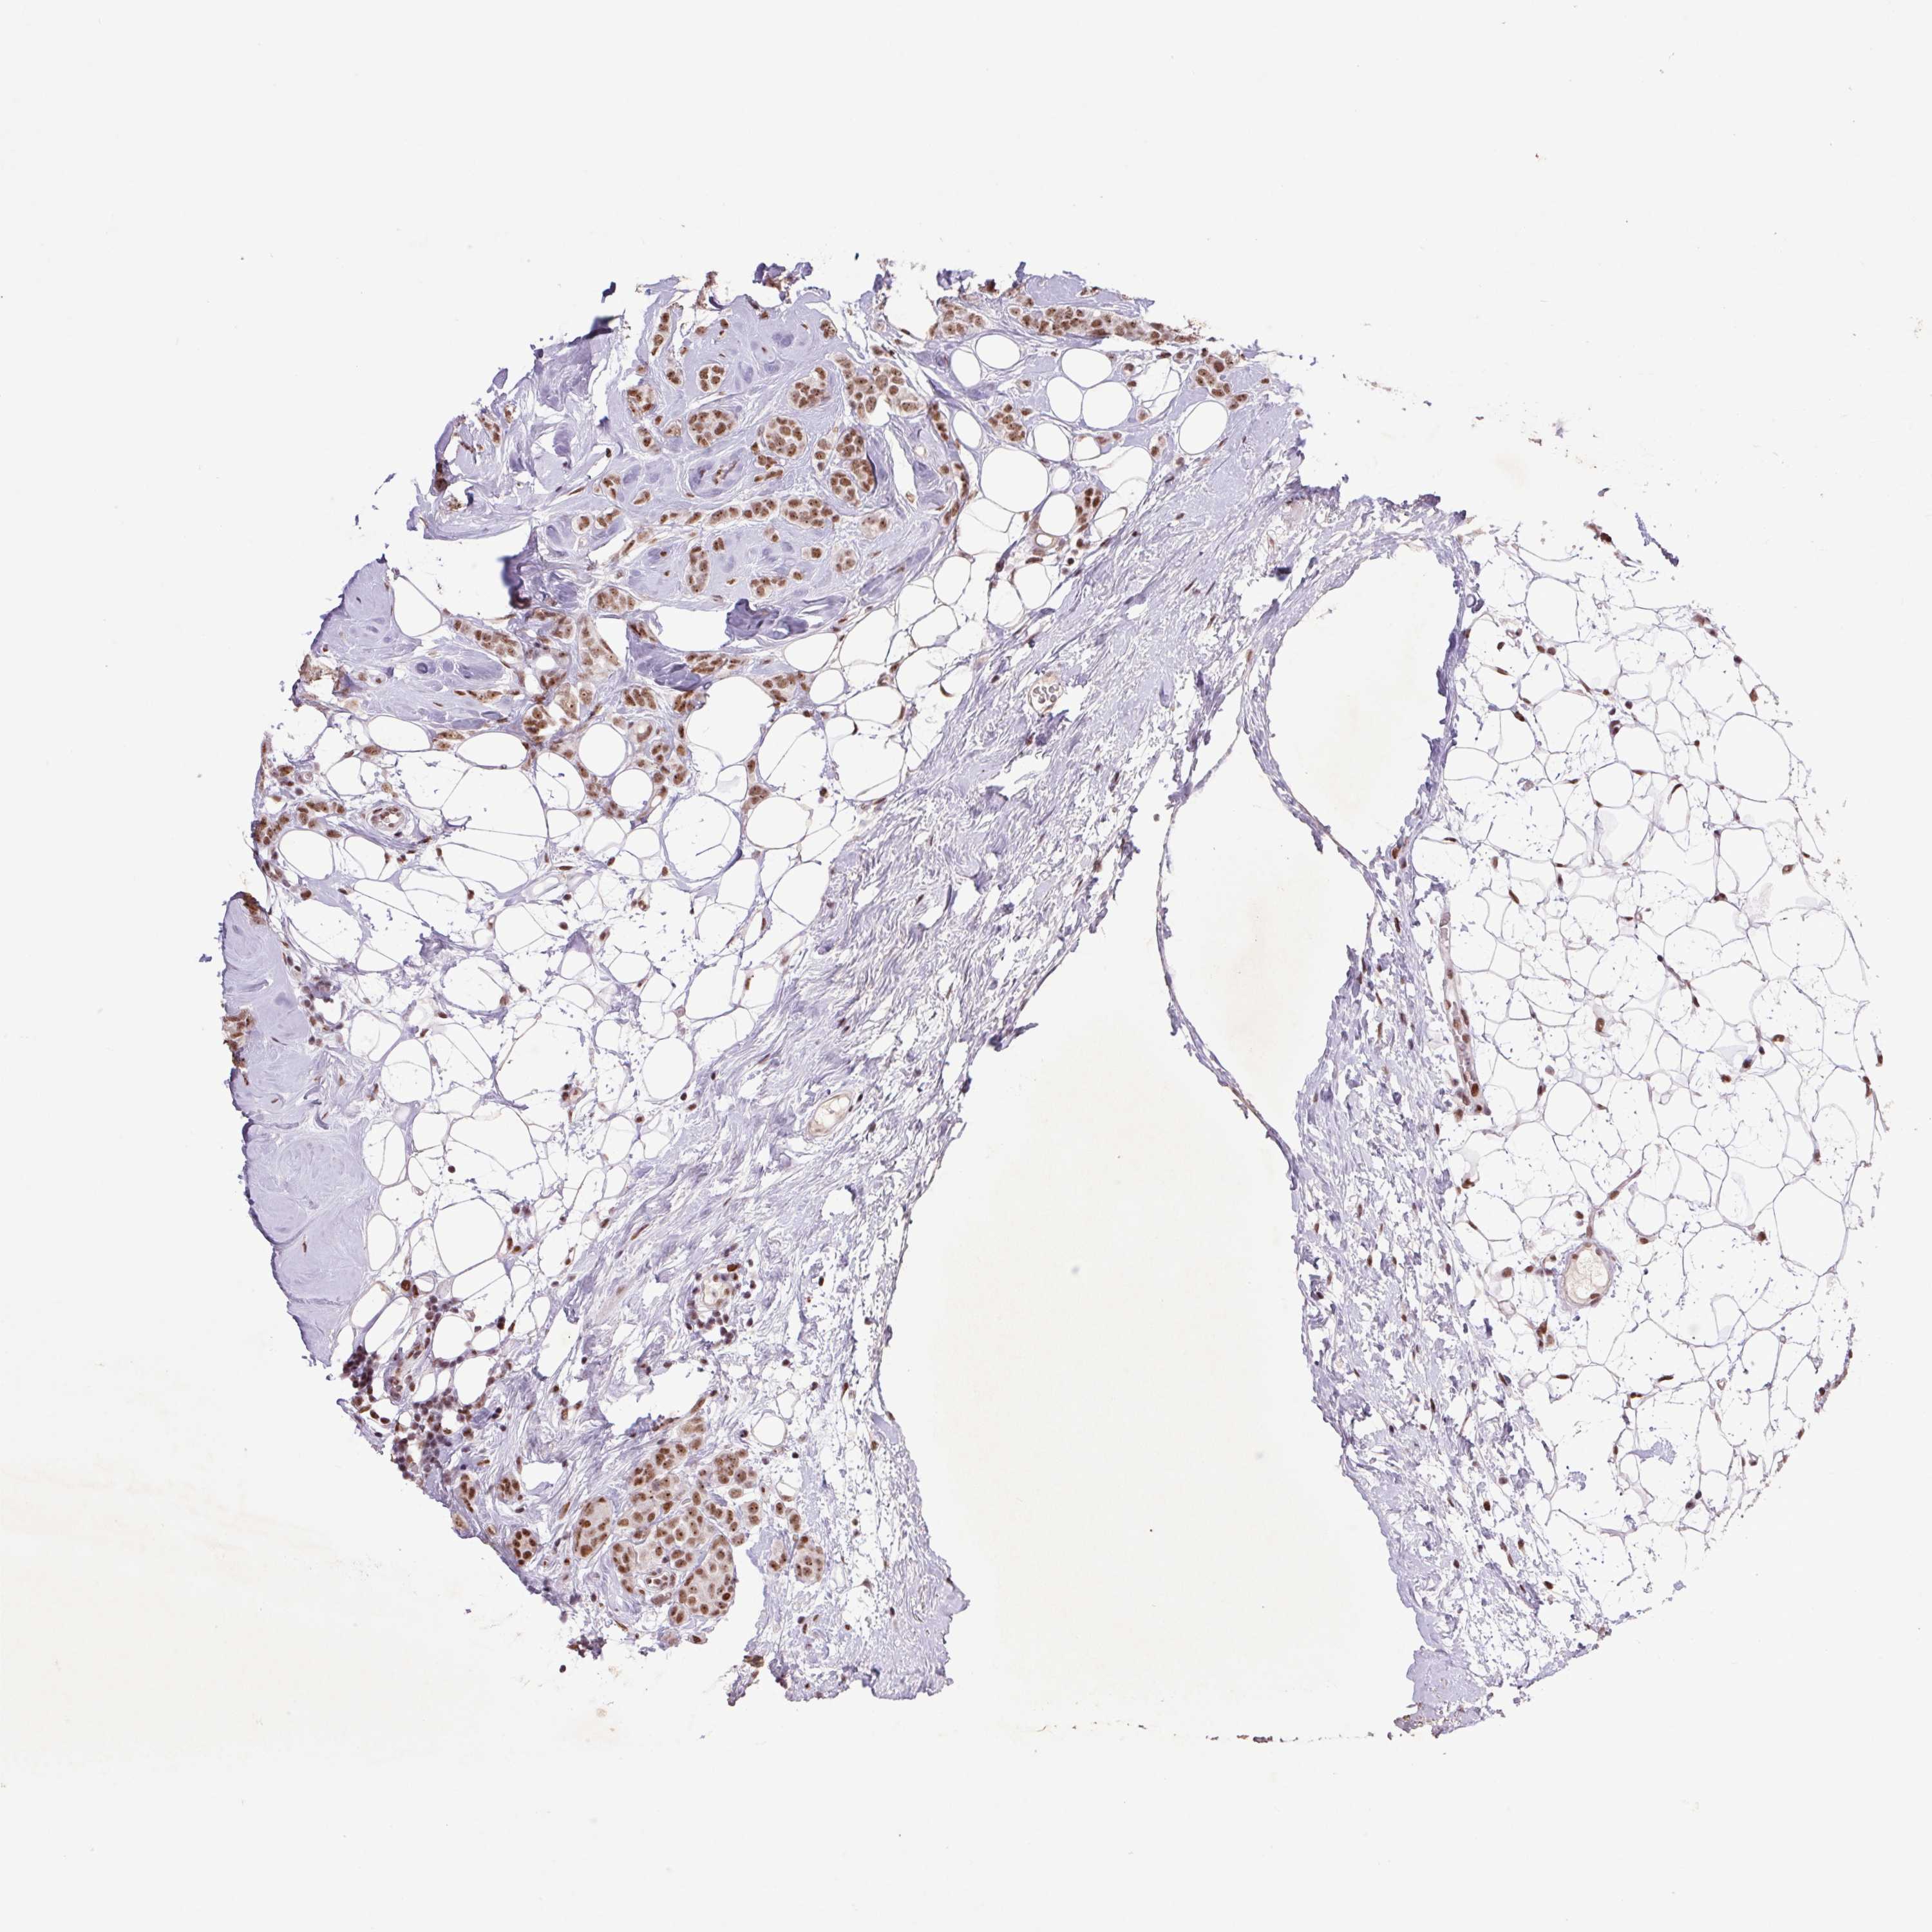

CANCER BREAST CANCER Show tissue menu

BRCA TCGA BRCA VALIDATION PROTEIN EXPRESSION

Breast cancer

Human cancer

Breast invasive carcinoma